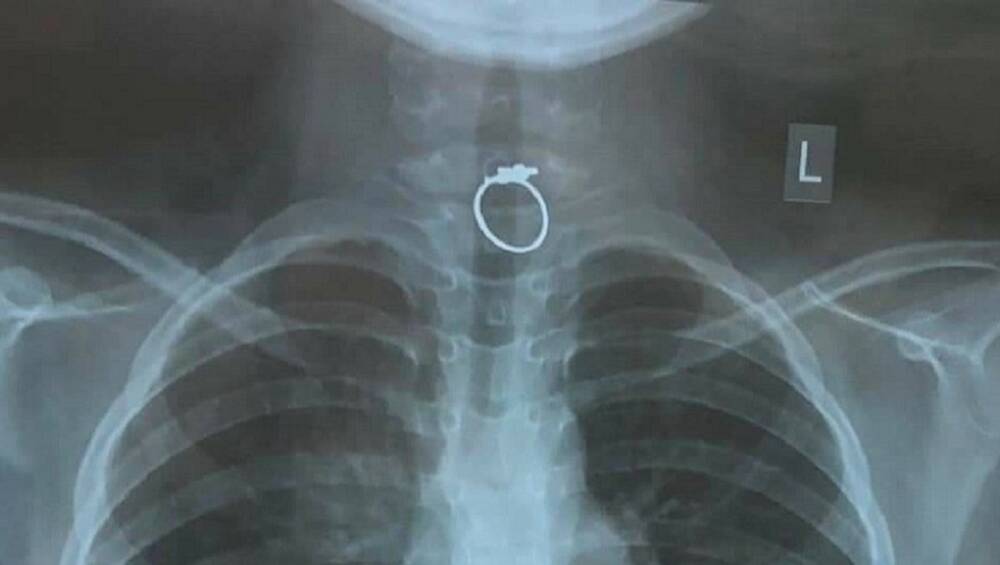

Ngày 14/2 (tức mùng 3 Tết Nguyên đán), kíp bác sĩ cấp cứu tại Bệnh viện Nhi đồng TP.HCM đã xử lý thành công trường hợp bé gái mắc dị vật trong họng, dị vật được phát hiện là một chiếc nhẫn kim loại có mặt hoa góc cạnh.

Theo đó vào trưa cùng ngày, các bác sĩ tại Bệnh viện Nhi đồng TP.HCM đã tiếp nhận trường hợp bé gái V.Y.N. (10 tuổi, trú tại Bình Tân) nhập viện trong tình trạng nuốt phải chiếc nhẫn.

Qua chụp phim cũng như là khám cấp cứu, các bác sĩ phát hiện một chiếc nhẫn kim loại đang kẹt ở vị trí 1/3 phía trên thực quản, ghim chặt vào niêm mạc.

Các y bác sĩ sau đó đã thận trọng rút nhẹ nhàng dị vật này ra. Đồng thời, cẩn thận kiểm tra vết thương các mô niêm mạc xung quanh. Các bác sĩ nhận định, nếu chiếc nhẫn tụt xuống sâu hơn, nguy cơ sẽ gây đâm xuyên vào ruột, thủng và tắc ruột nếu tiếp tục đi sâu vào ổ bụng.

Theo lời kể từ người nhà, bé V.Y.N. vừa được tặng chiếc nhẫn này. Bé cho vào mồm ngậm chơi và vô tình nuốt nhẫn và mắc kẹt trong cổ họng, gây nghẹn.